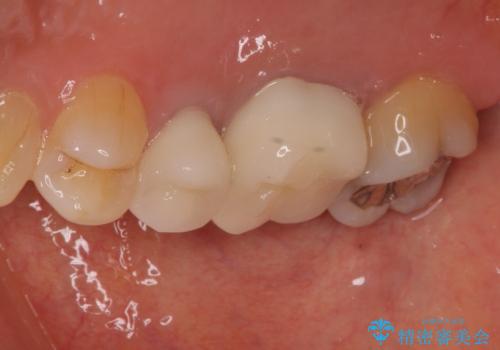

- 目立つ銀歯を気にして来院された患者様です。

奥歯を中心に銀歯が多く装着されており、一部の歯は咬合時に痛みを感じている状態でした。

必要な歯に根管治療を行い、オールセラミッククラウンにて補綴治療を行うこととしました。

一部根管治療では症状が改善しなかったため、歯根端切除術を行いました。